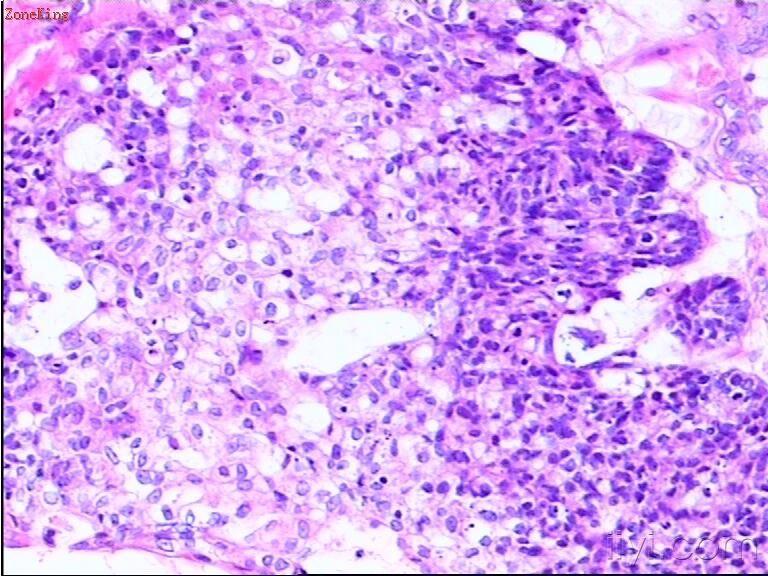

睾丸肿物,30岁,肿物位于睾丸白膜内,紧靠白膜,切面呈胶冻状。

部分区被覆上皮为粘液性上皮,考虑为粘液性囊腺癌;

30岁男子,睾丸肿块,有以下考虑:1. NSGCT2. 睾丸类癌。可以作为NSGCT的一个成分,也可以是来源于自身内分泌细胞的一个原发肿瘤或者是来自胃肠道肿瘤的一个转移瘤。 建议进一步做相关免疫组化(PLAP、AFP、HPL、NSE、PSA、β-HCG、CD30、EMA等待)或全面检查确诊。